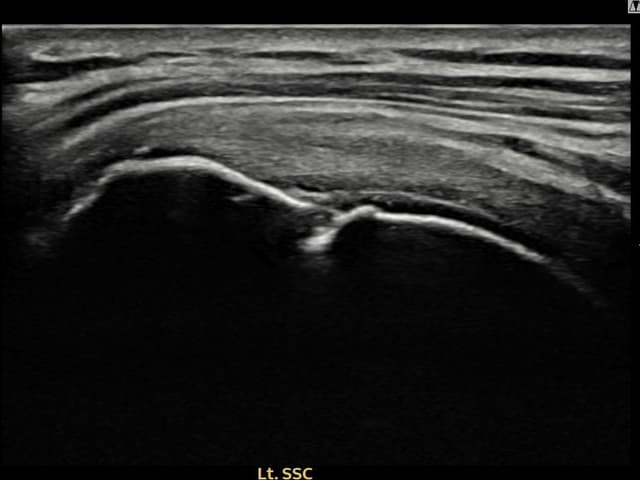

[촬영시기:22.09.02~22.11.15]

[어깨인대 축소봉합술] 좌측 어깨 부착부 부분파열로 팔을 들어 올릴 때마다 통증이 심해 내원하셨습니다.